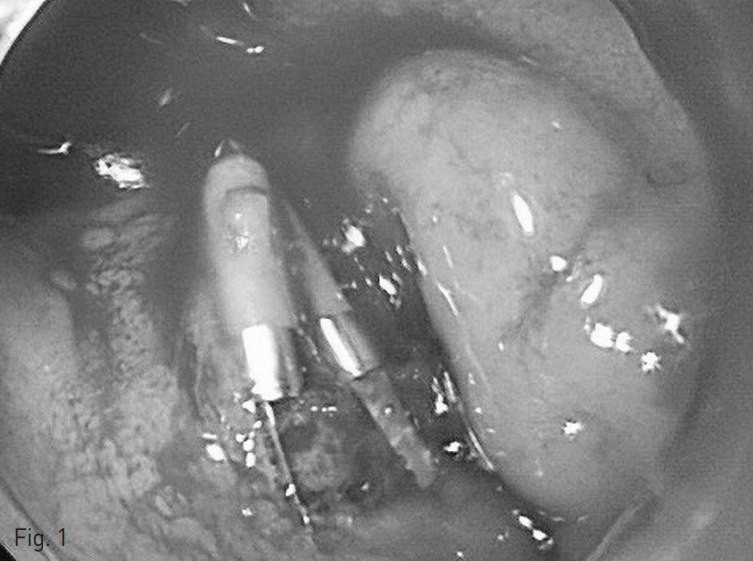

시행한 상부위장관 내시경에서 십이지장 궤양의 활동성 출혈이 관찰되었으며, 이에 대한 내시경적 치료에도 불구하고 출혈이 조절되지 않았다 (Fig. 1)

Fig. 1

Duodenal ulcer with active oozing bleding was noted on the endoscopy.